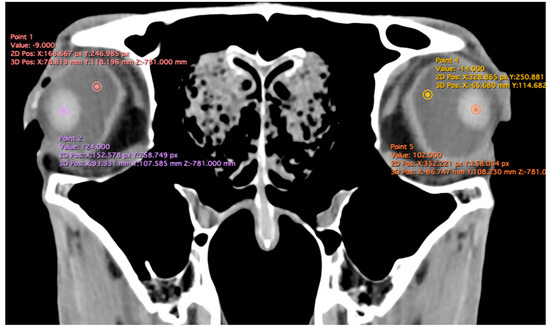

- Anterior chamber, posterior chamber, and lens densities: Attenuation values measured by placing regions of interest (ROIs) centrally in each structure (Figure 3).

Figure 3. Transverse multiplanar reconstruction (MPR) illustrating attenuation values obtained by placing ROIs centrally within each structure to measure the densities of the anterior chamber, posterior chamber, and lens.

Related to attenuation, the ROI (regions of interest) for measuring the attenuations of the anterior chamber, posterior chamber and lens densities are shown with different color circles (illustrated in Figure 3). The mean lens attenuation was 124.93 Hounsfield units (HU) with a range of 101–147 HU. The posterior chamber exhibited an average attenuation of −4.26 HU (range: −8 to −2 HU), while the anterior chamber displayed an attenuation of −8.05 HU (range: −14 to −4 HU).